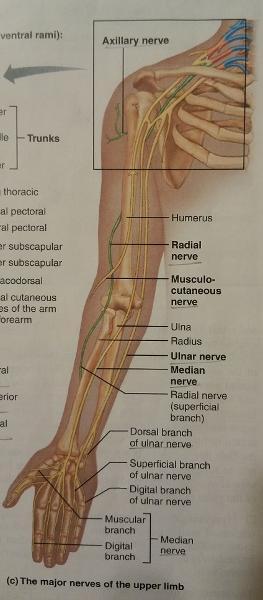

The brachial plexus after being rearranged consecutively into trunks, divisions, and cords, finally becomes subdivided into what 5 major peripheral nerves?

1. axillary nerve

2. radial nerve

3. median nerve

4. musculocutaneous nerve

5. ulnar nerve

The axillary nerve arises from the ventral rami of what cervical nerves and corresponding cord?

C5-C6 (posterior cord)

The axillary nerve serves what what 2 features (muscles and general feature of a certain body part)?

1. Muscles of the shoulder

2. Skin of the shoulder

The radial nerve arises from the ventral rami of what cervical and thoracic nerves and the corresponding cord?

C5-C8, T1 (medial cord)

1. The radial nerve serves the extensor muscles of what 2 body parts?

2. The radial nerve also serves what general feature of those 2 body parts along its course?

1. All the extensor muscles of...

- the arm

- forearm

2. The skin along its course

The median nerve arises from how many branches, and what are they?

2 branches: medial cord and lateral cord

The respective cords of the median nerve are composed of the ventral rami of which cervical and thoracic nerves?

Medial cord: C8, T1

Lateral cord: C5-C7

The musculocutaneous nerve arises from the ventral rami of which cervical nerves and its corresponding cord?

C5-C7 (lateral cord)

The musculocutaenous nerve supplies which group of muscles (of which body part) and another general feature?

Supplies the flexor muscles of the forearm and the lateral skin of the forearm

The ulnar nerve arises from the ventral rami of which cervical and thoracic nerves and the corresponding cord?

C8, T1 (medial cord)

1. The ulnar nerve supplies which group of muscles of which body part, and give an example?

2. The ulnar nerve also supplies another group of intrinsic muscles in which body part?

1. Supplies the flexor muscles in the anterior forearm (i.e. flexor carpi radialis).

2. Supplies all intrinsic muscles of the hand not served by the median nerve

The ulnar nerve also serves which general feature of the hand?

Skin of the medial third of the hand, both anterior and posterior surfaces

Identify the blanks.